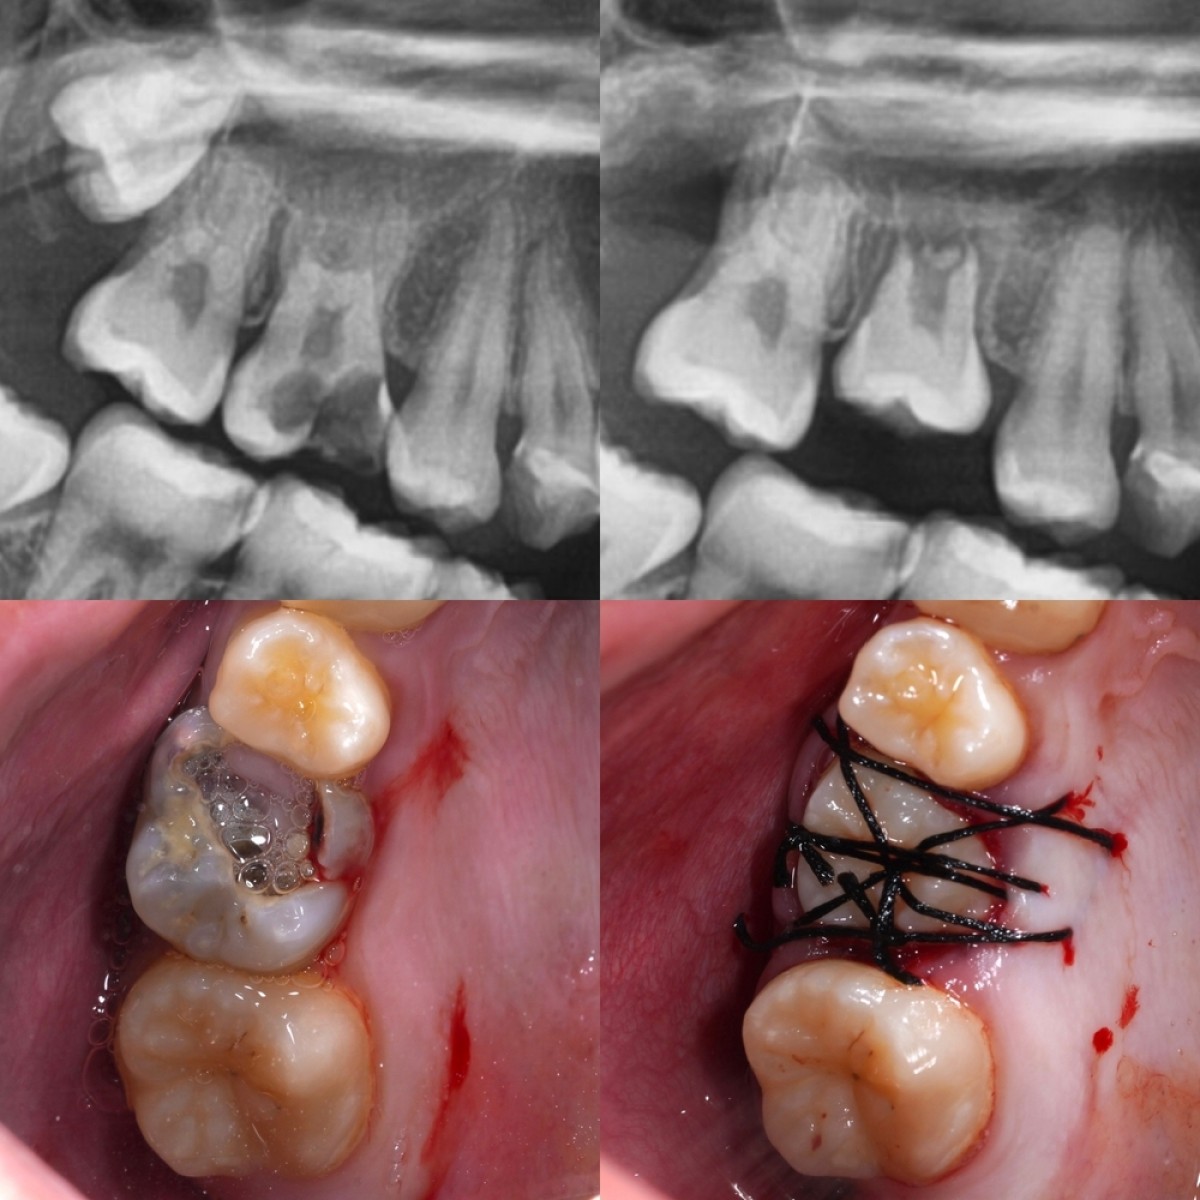

Tooth autotransplantation (AT) involves the surgical relocation of a tooth from 1 site in the mouth to another site within the same patient. This approach is a good option in a growing patient when dental implant placements or fixed bridges are not suitable and when preserving natural teeth is a priority. Tooth AT is a complex procedure that requires specialized skills from a multidisciplinary team with careful patient and tooth selection and treatment planning.

Success rates for tooth AT can vary depending on several factors, including the patient’s overall health, specific tooth involved, skill of the dental surgeon, and postoperative care provided. Long-term outcomes of autotransplanted teeth have been cited in the literature with impressive longitudinal follow-up spanning up to 26 years. Results of several systematic reviews showed survival rates from 75% through 98%.

Adoption of tooth AT has grown over the years, owing to advancements in dental techniques, improved patient outcomes, and increased awareness among both dentists and patients. Increasing awareness and availability of tooth AT to replace missing teeth can provide a natural and functional alternative to traditional prosthetic options. Tooth AT helps preserve the alveolar bone in growing patients and can offer excellent esthetic and functional outcomes.